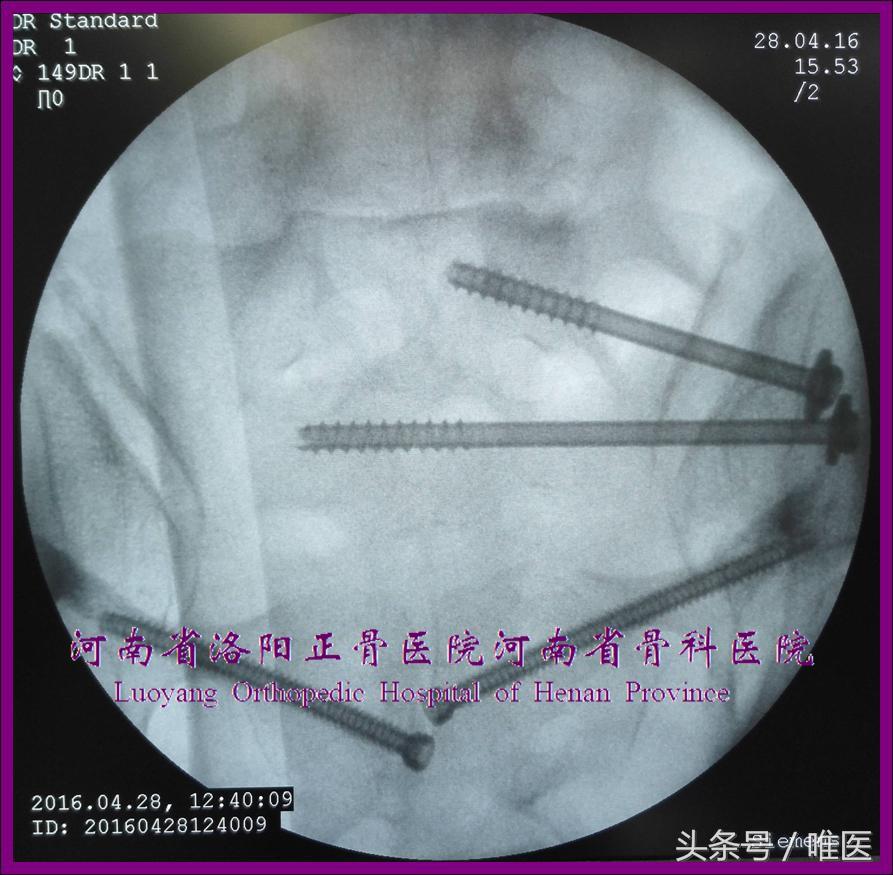

2. 骶2骶髂螺钉的置入技术

术前测量确定骶2节段是否存在安全置钉空间。如有安全空间,则按蔡鸿敏等所描述的置钉技术[22]进行置钉操作。(图13)

(1)确定进钉点 透视出标准骶骨侧位像,在此像上识别出骶神经根管前缘线、骶椎体前缘线、骶前孔上下缘等影像结构进而确定骶2节段的平向安全通道,将进钉点确定在其内。

(2)调整导针 将导针调整成一个点后轻浅打入骨质。

(3)确定导针的深度及指向 导针在骨盆出口位上应平行于上终板(或骶1双侧骶前孔下缘的联线),位于骶1及骶2骶前孔的中间(最少应打入椎体相对致密的骨质内,根据需要可打穿对侧髂骨外板)。骨盆入口位并非必须。

需要特别注意的是:当导针的进钉点未能成功调整成一个点并维持,则骨盆入口位亦不能提供可靠的指导,原因在于骶1/2椎体前缘存在上述三种关系,又在于骶1入口位及骶2入口位尚无可操作性。故为了避免骶髂螺钉突破骶2椎体前缘、骶2神经根管而需要再次透视标准骶骨侧位像确定螺钉位于骶2椎体前缘的后侧、骶2神经根管前缘线的前侧。

(4)置入骶髂螺钉:同上。

图13. 变异型上骶段骶2骶髂螺钉置入示例。